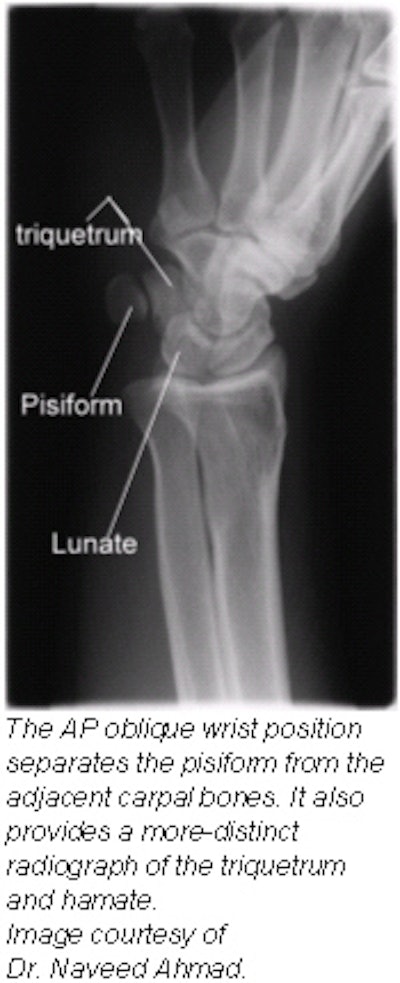

Positioning for AP oblique wrist projection (medial rotation)

- Place the cassette under the wrist and center it at the dorsal surface of the wrist.

- Rotate the wrist medially (intimally) until it forms a semisupinated position of approximately 45° to the cassette.

- CR: Perpendicular to the midcarpal area, it enters the anterior surface of the wrist midway between its medial and lateral borders.

Evaluation criteria

- Carpals on medial side of wrist.

- Triquetrum, hamate, and pisiform free of superimposition and in profile.

- Distal radius and ulna, carpals, and proximal half of metacarpals.

- Soft tissue and bony trabeculation should be visible.